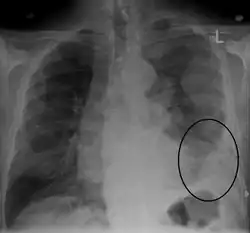

| CT scan showing a left sided mesothelioma with an enlarged mediastinal lymph node | |

More than 80% of mesothelioma cases are caused by exposure to asbestos.[3] The greater the exposure, the greater the risk.[3] As of 2013, about 125 million people worldwide have been exposed to asbestos at work.[13] High rates of disease occur in people who mine asbestos, produce products from asbestos, work with asbestos products, live with asbestos workers, or work in buildings containing asbestos.[3] Asbestos exposure and the onset of cancer are generally separated by about 40 years.[3] Washing the clothing of someone who worked with asbestos also increases the risk.[13] Other risk factors include genetics and infection with the simian virus 40.[3] The diagnosis may be suspected based on chest X-ray and CT scan findings, and is confirmed by either examining fluid produced by the cancer or by a tissue biopsy of the cancer.[2]

Imaging

Diagnosing mesothelioma is often difficult because the symptoms are similar to those of a number of other conditions. Diagnosis begins with a review of the patient's medical history. A history of exposure to asbestos may increase clinical suspicion for mesothelioma. A physical examination is performed, followed by chest X-ray and often lung function tests. The X-ray may reveal pleural thickening commonly seen after asbestos exposure and increases suspicion of mesothelioma.[15] A CT (or CAT) scan or an MRI is usually performed. If a large amount of fluid is present, abnormal cells may be detected by cytopathology if this fluid is aspirated with a syringe.[11] For pleural fluid, this is done by thoracentesis or tube thoracostomy (chest tube); for ascites, with paracentesis or ascitic drain; and for pericardial effusion with pericardiocentesis. While absence of malignant cells on cytology does not completely exclude mesothelioma, it makes it much more unlikely, especially if an alternative diagnosis can be made (e.g., tuberculosis, heart failure). However, with primary pericardial mesothelioma, pericardial fluid may not contain malignant cells and a tissue biopsy is more useful in diagnosis.[11] Using conventional cytology diagnosis of malignant mesothelioma is difficult, but immunohistochemistry has greatly enhanced the accuracy of cytology.